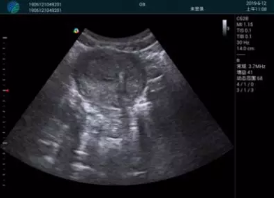

甲狀腺囊性結(jié)節(jié),囊壁鈣化,透聲好

甲狀腺囊性占位